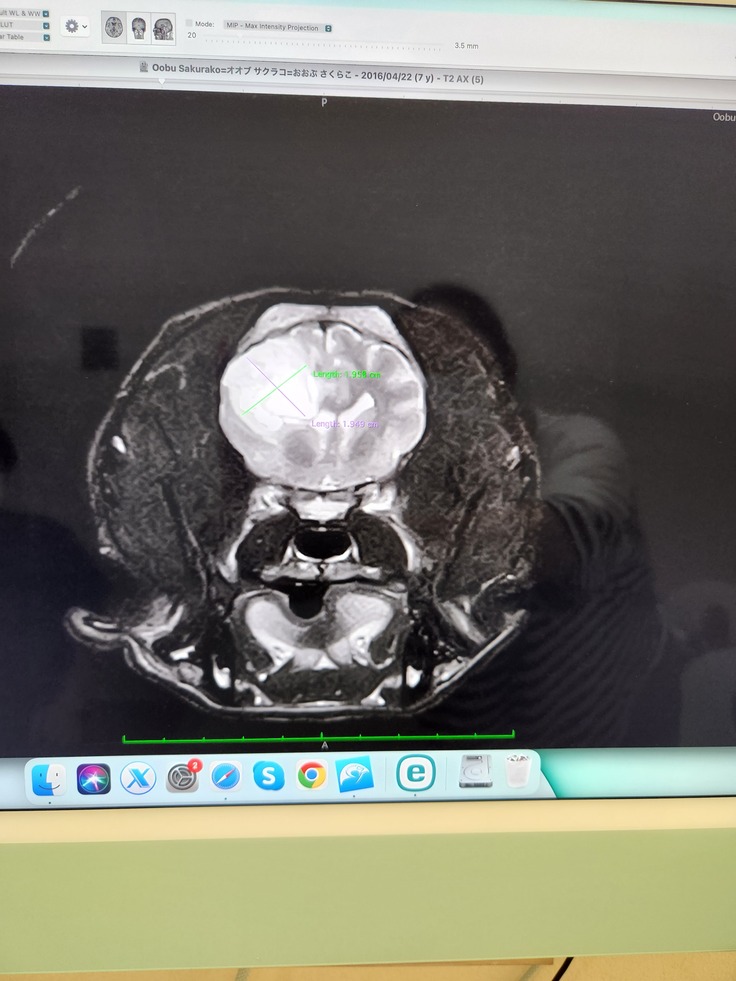

脳腫瘍摘出手術をして病理組織診断で希突起嘐細胞腫(びまん性グリオーマgrade3)と分かりました。

2023年8月1日に検査を受けに行きました。麻酔のリスクも心配でしたが無事に検査を終えて画像をみると2cmの腫瘍が見つかりました。

9月11日に放射線治療を受ける為の準備があり再びMRIなど受けました。

桜子の今の脳の状態の説明があり、残念

ことに取り切れなかった腫瘍がありました。

9月18日から放射線治療が週5日間のペース(計20回)で始まりました。